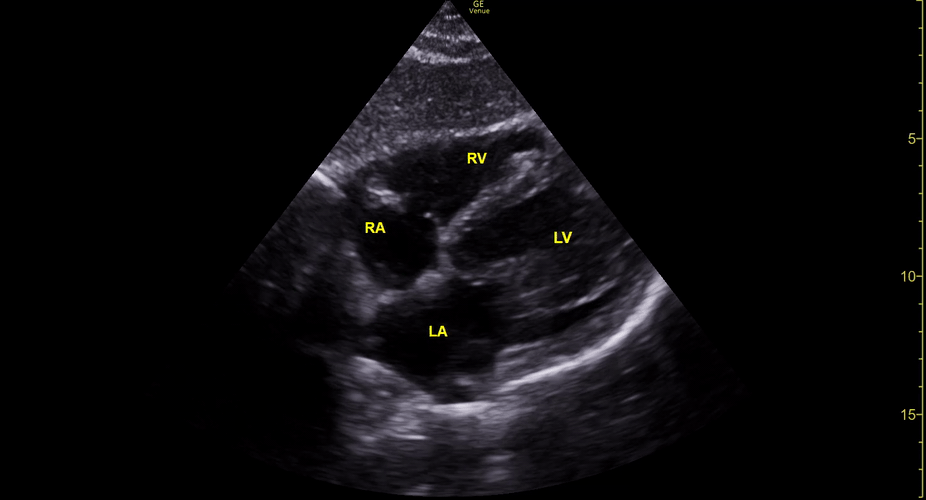

Equality: is the RV dilated or significantly impaired?

Normally, the RV is a low-pressure, thin-walled, high-compliance chamber that wraps anteriorly around the muscular, cone-shaped LV. The normal RV : LV diameter ratio is 0.6 : 1.

When the pulmonary artery pressure rises, the RV will dilate, altering the normal RV:LV ratio. Although sacrificing sensitivity, the use of equality (1:1 ratio) as a cutoff can achieve a specific estimation of RV strain. If imaged correctly by a trained operator, the presence of an RV:LV ratio > 1 is highly specific for RV strain.

RV dilation can be acute, chronic, or acute-on-chronic. However, in patients presenting with undifferentiated chest pain, shortness of breath, hypotension or syncope, the presence of any RV dilation should raise suspicion for acute pulmonary embolism (PE). Furthermore, in a patient in shock, the presence of RV strain may signal the need for aggressive therapy – emergency thrombolysis.

THE VIEWS

The A4C view provides an accurate chamber size comparison. However, achieving a proper A4C view (avoiding foreshortening or ballooning, and visualising the four chambers with a vertically oriented interventricular septum) can be a challenging exercise of image acquisition. Additionally, the PSAX view at the level of the papillary muscles shows both LV and RV side by side and is useful to assess function and size. When RV pressure is high, the septum will be pushed and flattened towards the LV, resulting in the characteristic “D-shaped” LV or “D sign”.